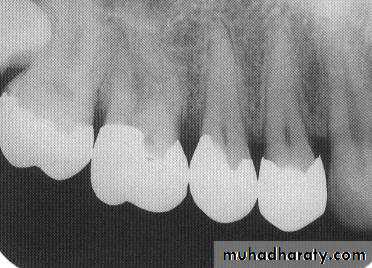

This radiograph shows (1) radiolucent restorations (composites) on the mesial surface of the lateral incisor and distal surface of the central incisor. Note that under both restorations is a base of radiopaque material. (2) The radiolucencies on the mesial surfaces of both central incisors are carious lesions.

Restorative Materials & Decay